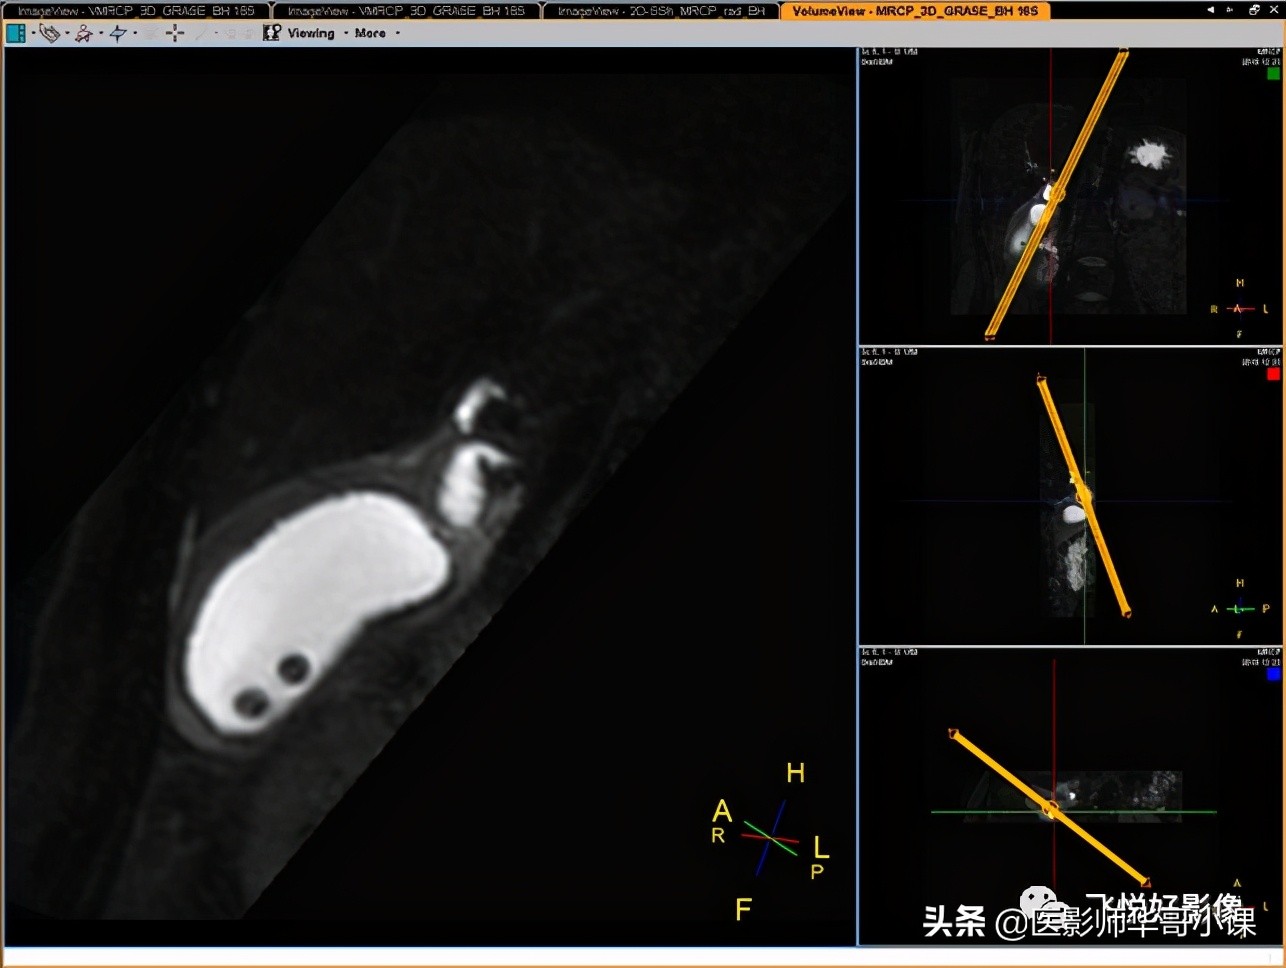

这个图像看起来和传统的3D_MRCP非常相似,但扫描时间却大有不同。3D_MRCP_BH只需要屏气16s即可完成检查。

3D_MRCP_BH可以进行3D重建,找到“责任病灶”。